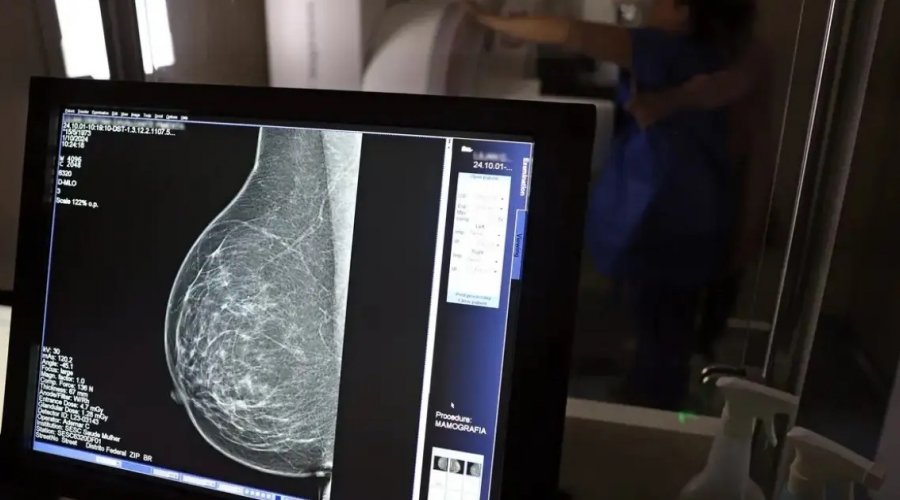

Foto: José Cruz/Agência Brasil

O presidente Luiz Inácio Lula da Silva sancionou a Lei nº 15.284, que amplia o acesso das mulheres ao exame de mamografia pelo Sistema Único de Saúde (SUS). Publicada nesta sexta-feira (19) no Diário Oficial da União, a nova norma assegura o direito ao exame para todas as mulheres a partir dos 40 anos, seguindo diretrizes do Ministério da Saúde.

A legislação modifica a Lei nº 11.664, de 2008, que trata das ações de prevenção, diagnóstico e tratamento dos cânceres de mama, colo do útero e colorretal no âmbito do SUS. Com a atualização, o exame passa a ser garantido mesmo para mulheres que não apresentem sintomas ou histórico familiar da doença, ampliando o alcance do rastreamento precoce.

Dados do Ministério da Saúde apontam que a faixa etária entre 40 e 49 anos concentra cerca de 23% dos casos de câncer de mama. A detecção antecipada aumenta significativamente as chances de cura e reduz a necessidade de tratamentos mais agressivos.

Segundo o ministro da Saúde, Alexandre Padilha, a medida representa um avanço histórico na política de atenção à saúde da mulher. O SUS realizou, somente em 2024, cerca de 4 milhões de mamografias de rastreamento e mais de 376 mil exames diagnósticos, reforçando a importância da prevenção como estratégia de cuidado e de salvamento de vidas.